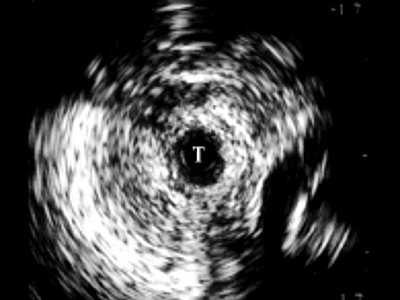

Рис. 2. Эхограмма нормального луковичного отдела уретры, Т - трансдуктор.

В мембранозном отделе (рис. 3) спонгиозная ткань не определяется, визуализируются повышенной эхогенности пластинка тазовой фасции, далее мочеполовая диафрагма с проходящими сосудами. При проведении датчика в область простатического отдела хорошо определяется предстательная железа, ее транзиторная, центральная, частично периферическая зоны, капсула.

Рис. 3. Эхограмма нормального мембранозного отдела мочеиспускательного канала.